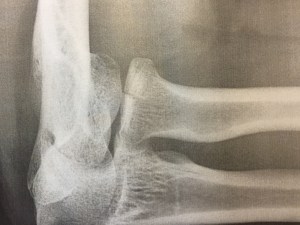

Vaatimattomassakin alamäessä vauhti karkaa nopeasti lapasesta, eikä ensimmäisestä laudan päälle astumisestani ole kulunut varttiakaan, kun olen jo pannuttanut itselleni luunmurtuman. Tehokasta liikuntaa! Vamma tuntuu tosin ihan tavalliselta pikku kolhulta aluksi, niin että jatkan vielä, kunnes kaadun toistamiseen. Mieleen juolahtaa, että niin internet kuin ystäväkin ovat suositelleet kypärän ja muiden suojusten käyttämistä näin aluksi, ja päätän lopettaa tältä erää, kun olen vielä hengissä.

Illan mittaan kolhu alkaa tuntua murtumalta. Kyynärpää rutisee ja poksuu ja turpoaa, ja loppuillasta kädellä ei oikeastaan voi tehdä paljon mitään, ei edes syödä, koska se ei koukistu tarpeeksi.

Värttinäluun päässä on tosiaan murtuma, mutta osat ovat paikoillaan. Jos kaikki menee hyvin, niin levolla selvitään. Mutta silti harmittaa. Tämän kesän kiipeilyt ja melomiset taisivat olla nimittäin tässä. Eniten potuttaa, että vamma johtuu pelkästä tyhmyydestä: niistä suojuksista oli sanottu. Mutta kuten kaverini Jani kommentoi: Kovat jätkät eivät käytä suojuksia. Eivätkä kuuntele neuvoja.